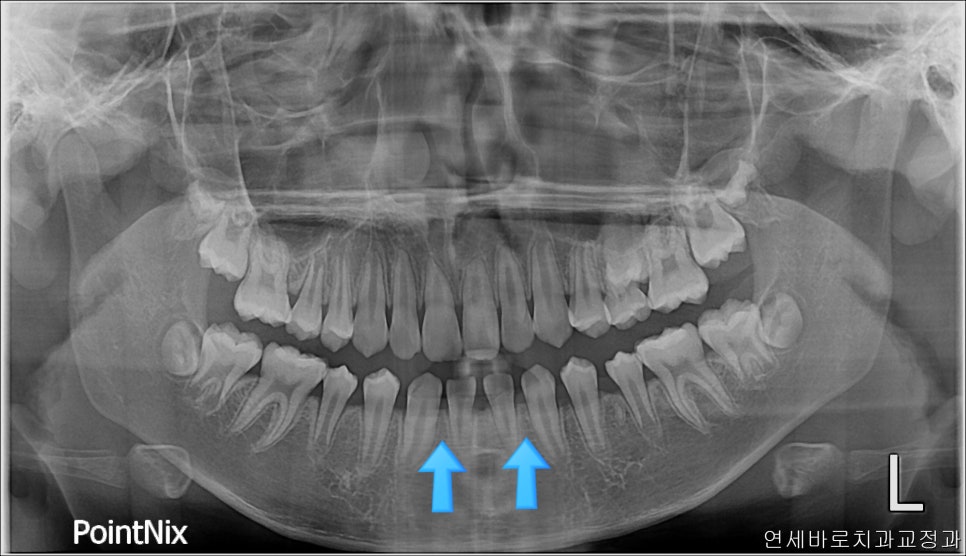

여기 두개의 치아가 더 있어야 했지만

이 친구는 약간의 돌출도 보이고 있었기 때문에 위쪽 치아를 두개 발치했었습니다.

오랜 시간이 지난 뒤 엑스레이에서도 부작용이 관찰되지 않고 잘 유지되고 있네요